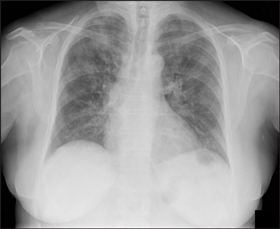

4 Chest x-rays showing typical abnormalities found in patients hospitalised with influenza, 17 June to 31 July 2009

Patient with pandemic (H1N1) 2009 influenza showing bilateral interstitial and airspace opacity. |